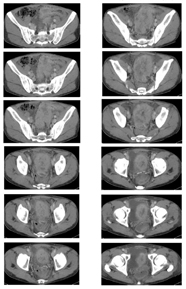

CT検査でS状結腸に約8 cmの腫瘤を認めサブイレウスの診断となり、緊急ストマ造設術を施行した。

- ■ CT検査でS状結腸に約8 cmの腫瘤を認め遠隔転移はなし

治療開始から9週(3コース)経過後CT所見で原発巣縮小を確認(PR) |